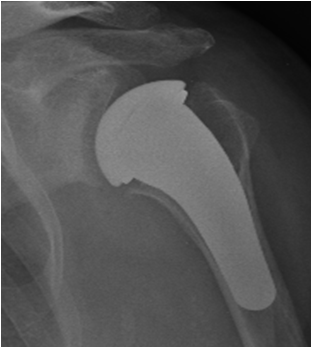

Componente omerale – Il tipo di protesi più utilizzato è composto da uno stelo che fa presa nel terzo prossimale della diafisi omerale e da una calotta con superficie sferica. Per impiantare questa protesi si deve sezionare ed eliminare la testa dell’omero degenerata e poi “scavare” opportunamente il canale omerale per inserire stabilmente lo stelo (ad incastro o con cemento). L’esperienza con questi tipi di protesi cosiddette “anatomiche” risale agli anni ’50. Rappresentano tuttora il tipo di impianto più diffuso (fig. 9).

Componente glenoidea – Quando è degenerata anche la superficie articolare della scapola (la glena o glenoide), ai tre tipi di protesi omerali già visti – anatomica, di rivestimento, emicefalica – si accoppia una componente scapolare con superficie concava, che può essere composta da una base metallica (il “metal back”) su cui si incastra una sorta di scudo in polietilene (fig. 9 e 13); oppure può essere tutta in polietilene (fig. 12).